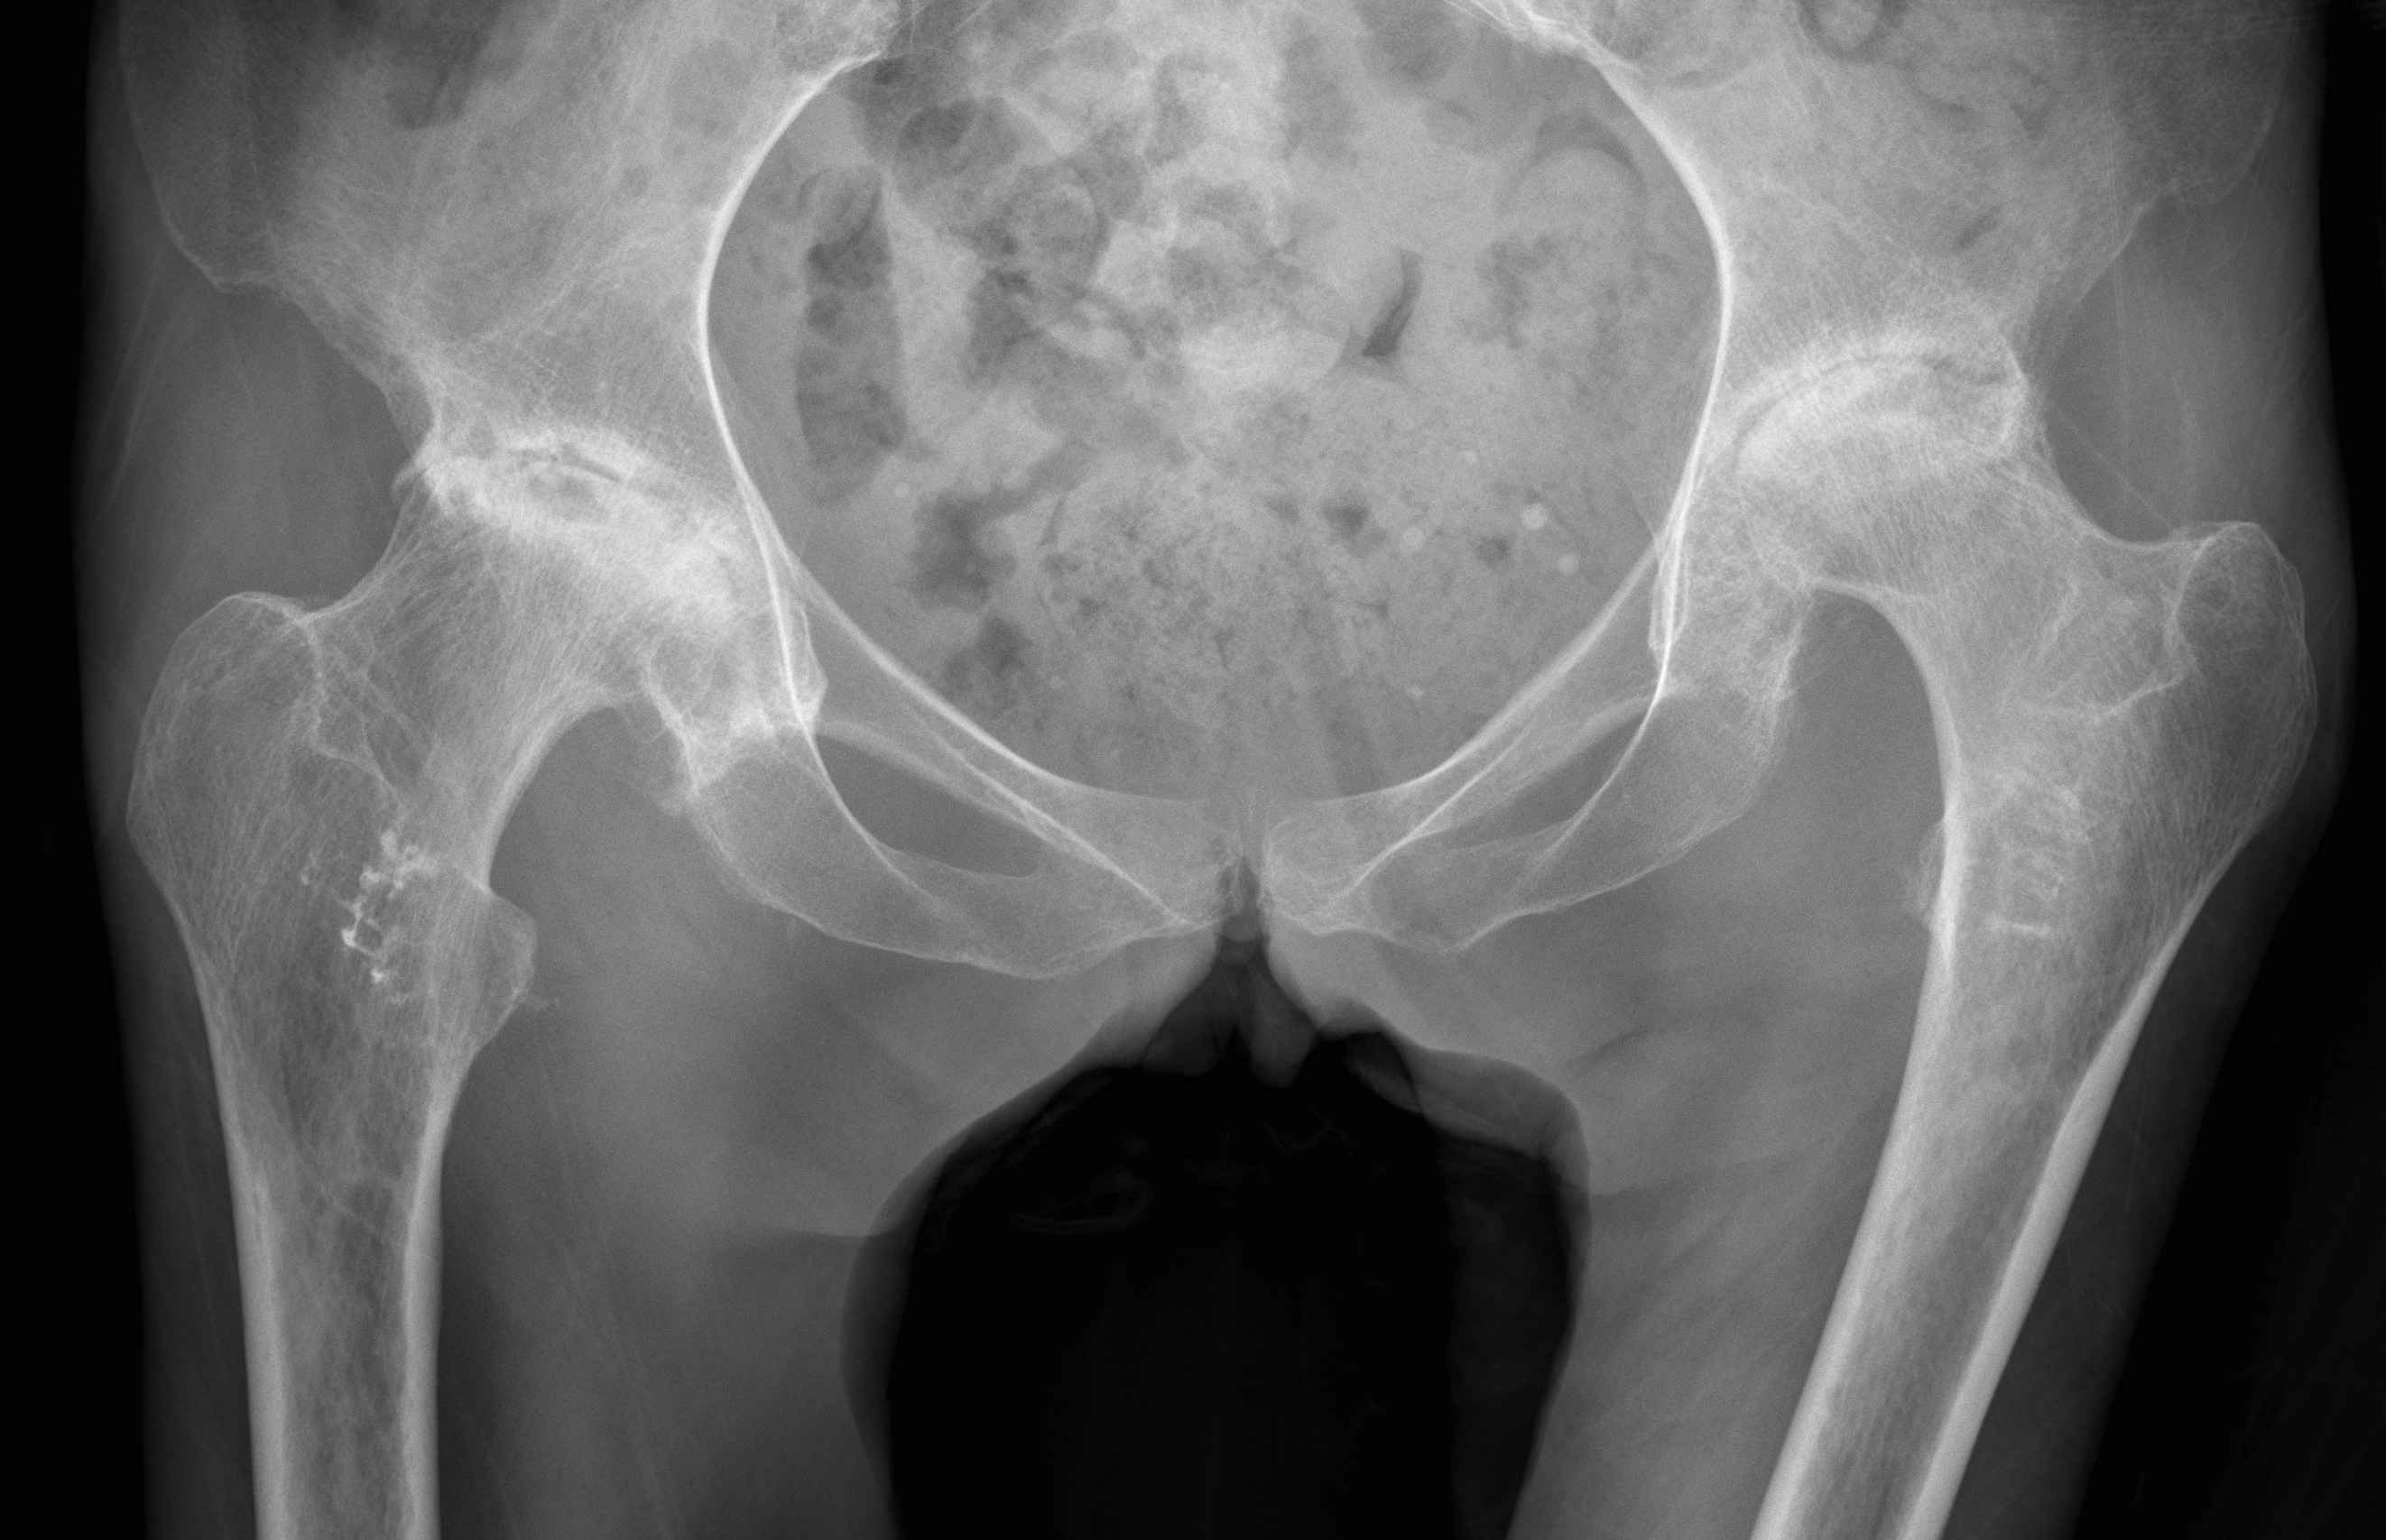

AP pelvis

- both femurs IR 15o / compensate for anteversion

- symmetrical abduction / adduction of femurs

Abnormal femur position

Pelvic landmarks

- inferior aspect of ischial tuberosities

- tear drop

- center of rotation

Femoral landmarks

- lesser tuberosity